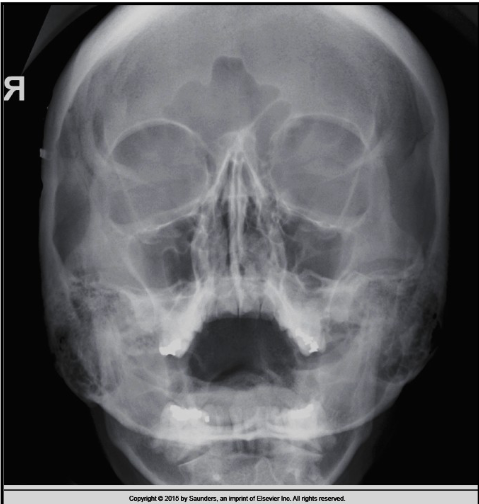

what is the issue here

A

way too much angle

Q

what is the correction

20-25 deg more caudad

lift chin to change OML by 20-25 deg